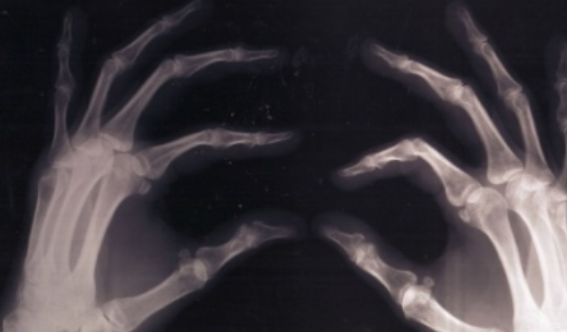

La osteoporosis que se estima afecta a 10 millones de mexicanos y la fragilidad en los huesos de los menores, son las principales consecuencias de una dieta carente de calcio. Esto aumenta el riesgo de fracturas de cadera, codos, muñecas, rodillas y tobillos.

Los niños con restricción crónica de lácteos tienen baja ingesta de calcio, y eso ocasiona una masa ósea pobre con tres veces mayor riesgo de fracturas y a más temprana edad que los niños que sí consumen esos productos, señalaron especialistas en nutrición.